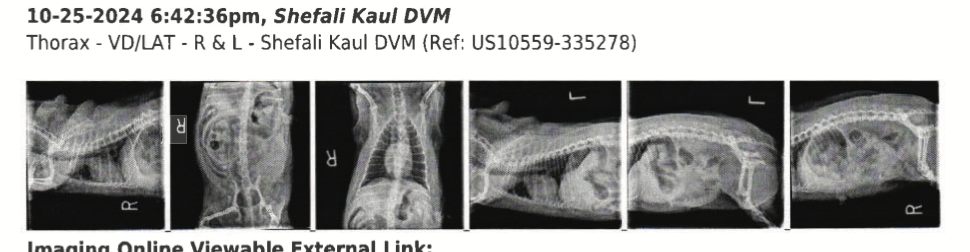

According to the report, Sumo jumped a fence, bit Brandy, then pulled Margarita from Castillo’s arms and threw her onto the street. Both dogs were treated at the Veterinary Specialty Center in Lynnwood.

Veterinary records show Margarita suffered minor hip and rear wounds. Brandy, however, had several abdominal punctures. Due to concern over potential penetration of an internal organ, veterinarians recommended emergency surgery costing more than $11,000 – in addition to $5,000 Castillo already spent on tests and treatment for both dogs that night.